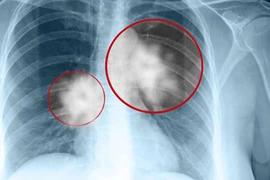

Không hút thuốc lá sao nghệ sĩ Hán Văn Tình vẫn bị ung thư phổi?

Không hút thuốc lá nghệ sĩ Hán Văn Tình vẫn bị ung thư phổi - nguyên nhân do đâu?

(Kiến Thức) - 11h20 ngày 4/9, nghệ sĩ Hán Văn Tình qua đời vì căn bệnh ung thư phổi. Những phút cuối trước khi rời cõi tạm của "lão Quềnh" gây xúc động.

(Kiến Thức) - Nghệ sĩ Trà My vừa chia sẻ, nghệ sĩ Hán Văn Tình đã qua đời vì bệnh ung thư vào lúc 11h20 trưa nay (4/9) tại nhà riêng, hưởng dương 59 tuổi.